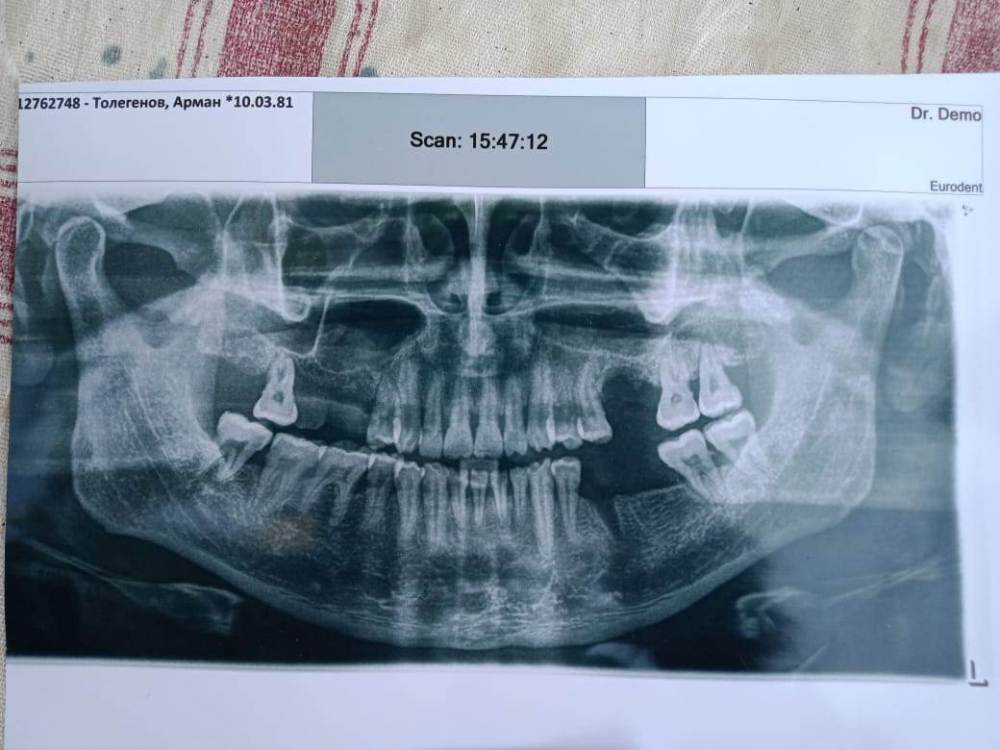

вылечили зуб и через пару месяцев начал болеть потехоньку.  пришлось оторвать зуб.  в зубе  снизу на корне была   белая   тонкая  как нить. не обратил внимание.  но  боль не перестает. и лунка  долго востанавливается так сказали хирурги  когда делал панорамный снимок  . стало еще больнее  и настолько больно  что и слово не сказать. как оторвал прошло больше 3-рех месяцев  вот и мучаюсь . симптомы такие -   когда  затягиваю сигатеру  наступает боль. боль в области 5 зуба нижней челюсти.  боль   острая  с неким ощущением холодка. думаю обратится ЧЛХ.     заранее хотел тут  узнать или проконсультироватся в чем может быть такая проблема.  если есть тут професура  и хирурги .  и еще  я растратился  просто так  на две остальный зубы  про   словам других стоматологов и пришлость удалить не те зубы а причина  в другом ... помогите найти причину.  БУдУ ОЧЕНЬ ВАМ  ВСЕМ БЛАГОДАРЕН !   эта уже  стала проблемой  в моей жизни ...

1622306037089.jpg